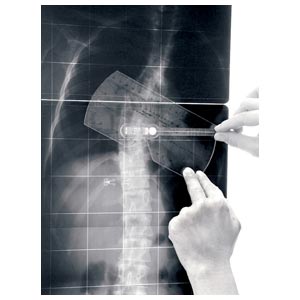

Strumento per la misurazione dell'angolo di Cobb e del gibbo. L'inclinometro è costituito da 1 elemento quasi-rettangolare di plexiglas recante una scala goniometrica, al cui centro è posizionata una piccola asta libera di ruotare e recante una bolla; l'estremità libera dell'astareca l'indice di lettura per la scala goniometrica. Il lato più lungo del rettangolo presenta una rientranza per renderne più agevole l'applicazione sul paziente (nel caso in cui le spinose siano sporgenti).

L'inclinometro è uno strumento manuale, normalmente utilizzato in due situazioni cliniche: • nella misurazione dell'angolo di rotazione del tronco durante il test di anteroflessione • nella misurazione dell'angolo di Cobb sulle radiografie (sia in proiezione AP che LL), quindi sia nella scoliosi che nella cifosi/lordosi.

L'angolo di Cobb è dato dalla somma dei due angoli di inclinazione delle limitanti. La misurazione dell'angolo è più veloce del metodo tradizionale (è sufficiente accostare lo strumento alle vertebre limite e leggere il valore sulla scala graduata), non richiede strumenti aggiuntivi, non deteriora le radiografie, semplifica la misurazione eliminando quindi alcune possibili cause di errore.

Un vantaggio dell'inclinometro sugli altri strumenti è dato infine dalla possibilità di misurare sia l'angolo di rotazione del tronco (gibbo) sul paziente, sia l'angolo di Cobb sulle radiografie con un solo semplice strumento.